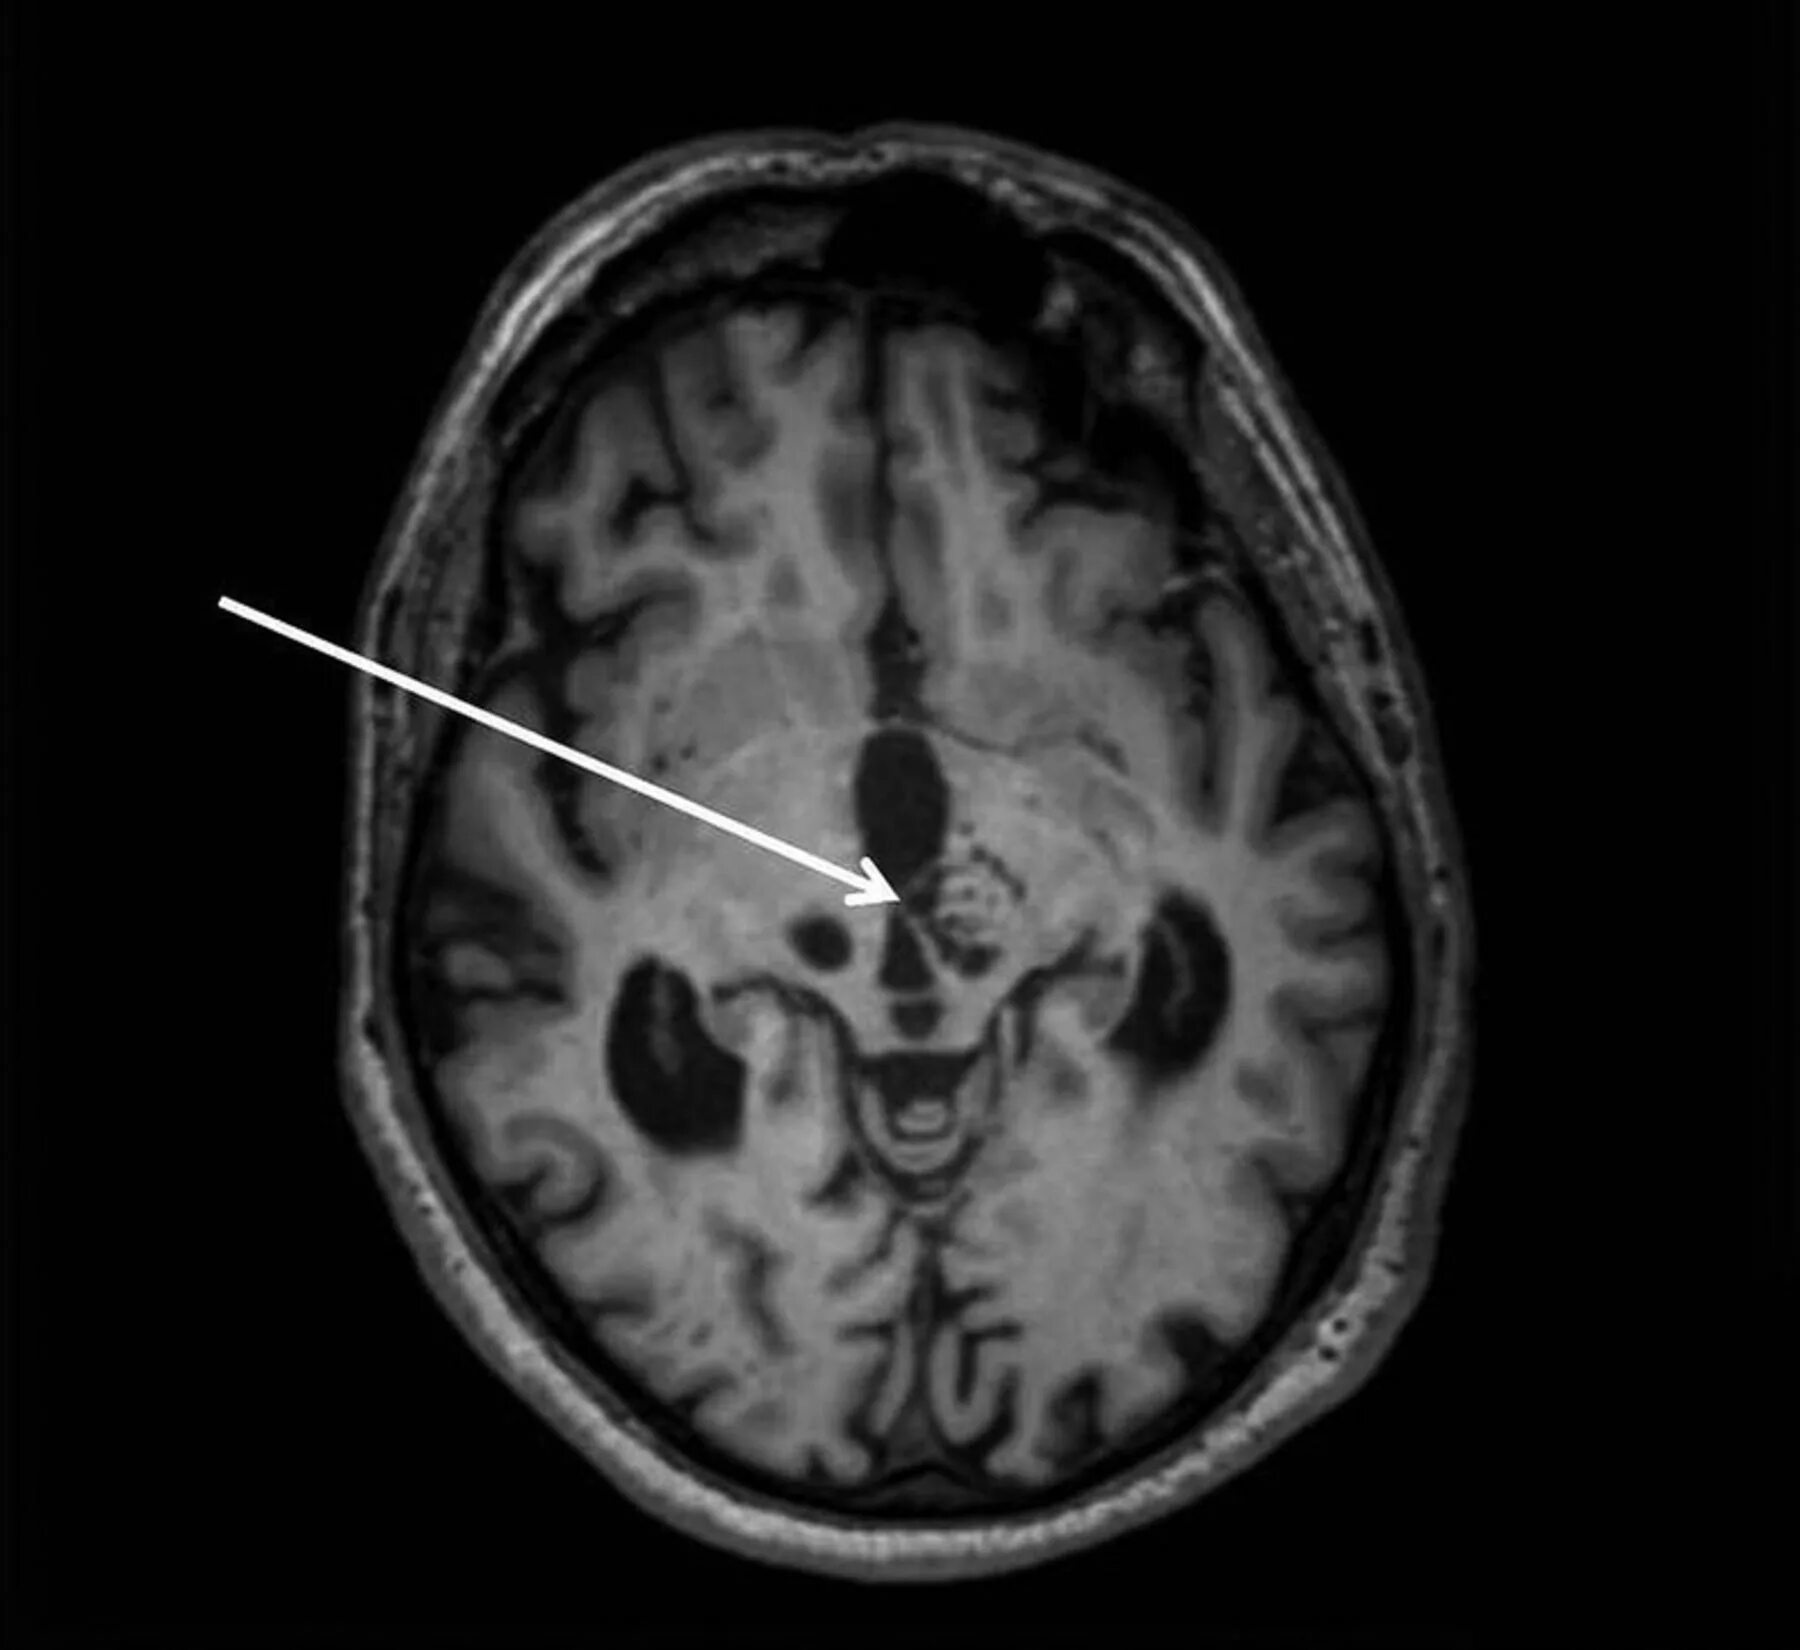

Что значит пространства вирхова робина